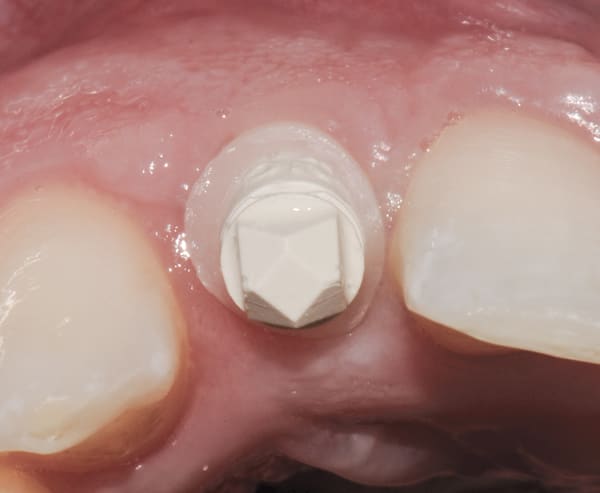

Step 8—The provisionals were removed from the patient’s implants and the custom scan bodies were attached. Finally, the composite resin collar was prepared to the gingival tissue level with a flat-nose high-speed diamond (Figure 16). The scan body will provide the laboratory with a prescribed soft-tissue level in the digital impression (Figure 15, right image). This is the most critical step.

Both provisional restorations were removed, the definitive abutments were connected, and the abutment screws were torqued to 35 Ncm. The accuracy of the abutment margins at the gingival level, as transferred from the original custom scan body, is demonstrated in Figure 24. A cotton pellet and elastic, single-component, light-cured resin was placed to close the abutment access hole and light cured. The definitive restorations were cemented with radiopaque glass ionomer luting cement (Figure 25 through Figure 29).